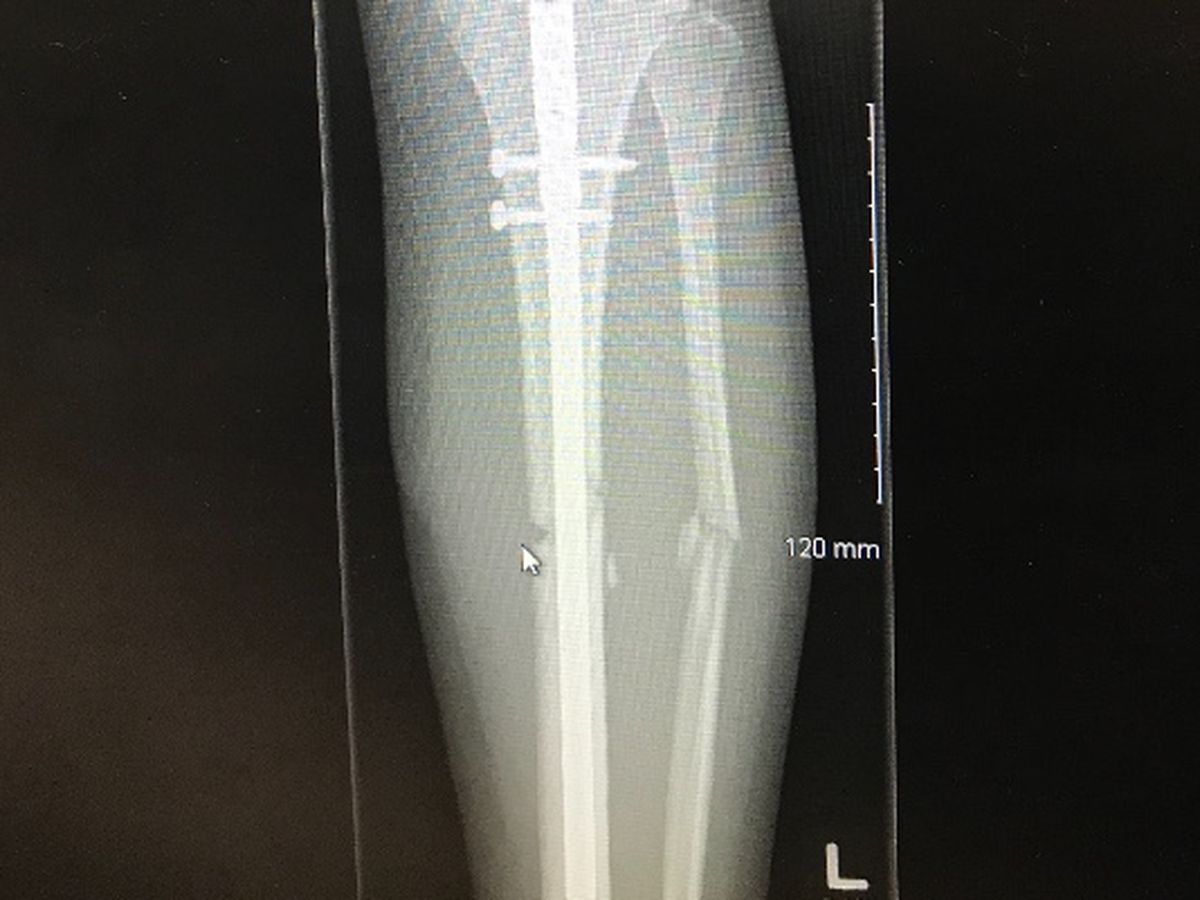

Hello, I just had a motorcycle accident and is trying to raise some money to help me with my medical bills and get up on my feet once again. Anything will be  appreciated